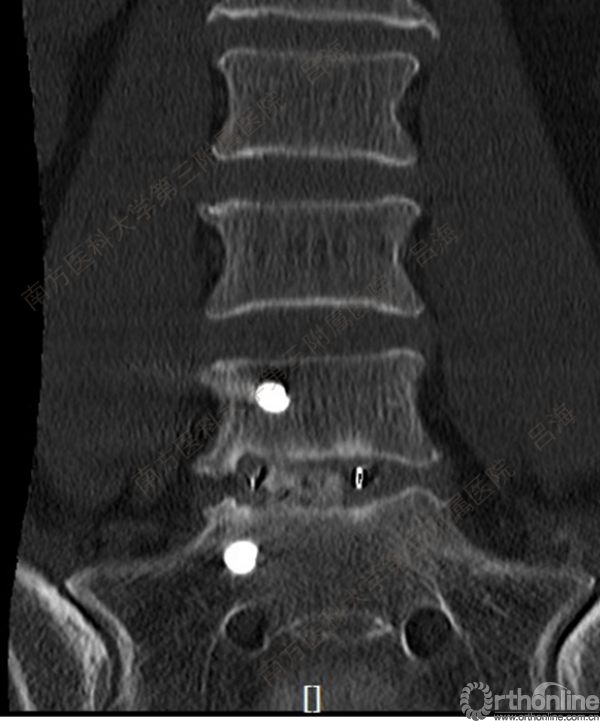

随着社会老龄化进程加快,胸腰椎退行性病变的治疗已经成为脊柱学术界的一个热点话题。MIS-TLIF手术可以治疗多种不同的胸腰椎退行性疾病,南方医科大学第三附属医院吕海教授结合病例为我们一一展示了该术式在治疗不同胸腰椎疾病时的具体手术过程。